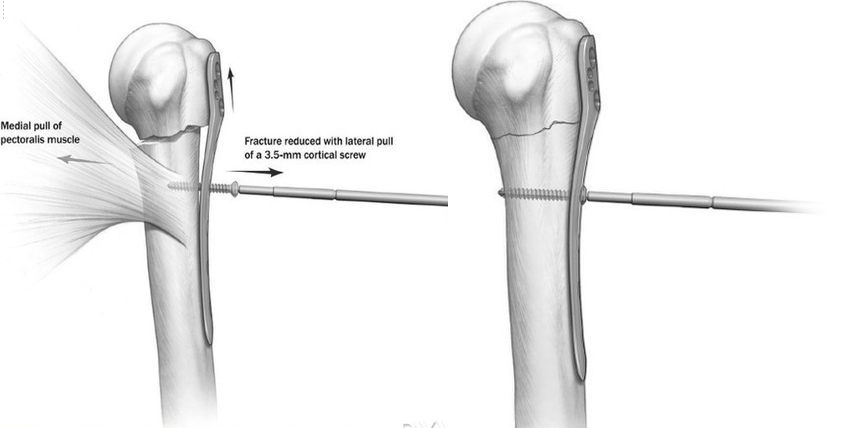

由于胸大肌的牵拉,颈部骨折的病例肱骨干通常都向内移位。通过纵向牵引并向外侧牵拉常可部分复位,如同时将肱骨干骨折块逐渐向钢板靠拢便可获得满意的复位。为了达到这一目的,先将钢板固定在肱骨头外侧面,而此时骨干可能仍然存在向内移位,在骨折线远端的第一个螺钉孔置入一枚3.5mm皮质骨螺钉将肱骨干向外提拉复位。

如果肱骨头骨折块存在内翻移位,可同时牵拉头部的缝线使其复位。应用上述方法时,将钢板放置在适当的位置非常重要。拧紧3.5mm皮质骨螺钉将内移的骨干复位后,可能会使钢板在大结节上轻度上移。因此,预计到这一偏移,一开始将钢板放置在大结节上时就应该稍往远端一些。如果钢板放置的位置太偏上,则必须重新调整。

放置肱骨近端锁定钢板时,可借助瞄准装置确定理想的位置:距离肱骨大结节上缘5-8mm并位于结节间沟外侧2-4mm,确保钢板与肱二头肌长头腱之间有足够的缓冲区。置入钢板时如果必要的话可在三角肌止点处做适当的剥离。应用影像增强器确认钢板位置和骨折的复位是否满意。为了避免撞击,必须注意不要将钢板放置得太靠近段。第一枚螺钉通常为3.5mm皮质骨螺钉,应用标准操作规程置入靠近骨折端的螺孔内。这一螺钉可对抗胸大肌对肱骨干骨折块的牵拉。拧紧螺钉时,必须留心,确保钢板的远端部分位于肱骨干的正中。